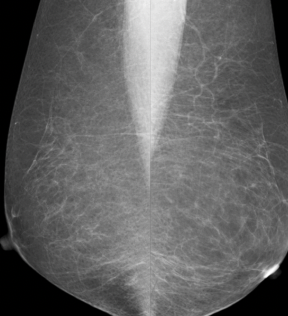

multiple round masses of varying size in both breasts. masses are very well defined, have a black halo (benign appearance on mammography)

Appearance in keeping with cysts however requires an ultrasound to make a definitive diagnosis